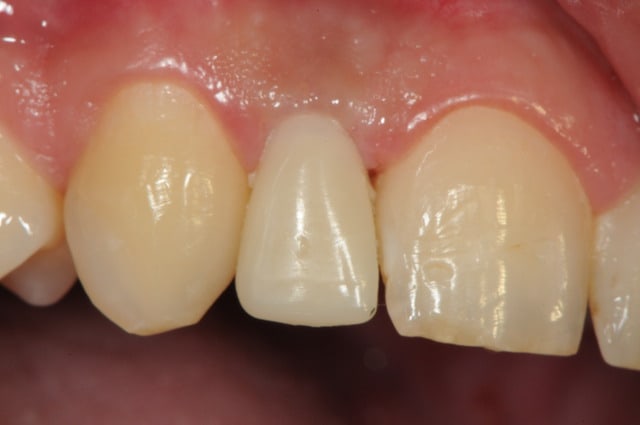

photos finish!!!

à noter...avec le flash...difficile de rendre le "naturel" de ces restaurations(teintes très claires)...après petite gingivoplastie pour harmoniser la hauteur des collets...(surtout pour 12...)

01/09/2010 à 16h54

- couronne en place (petite compression gingivale)

fin du traitement